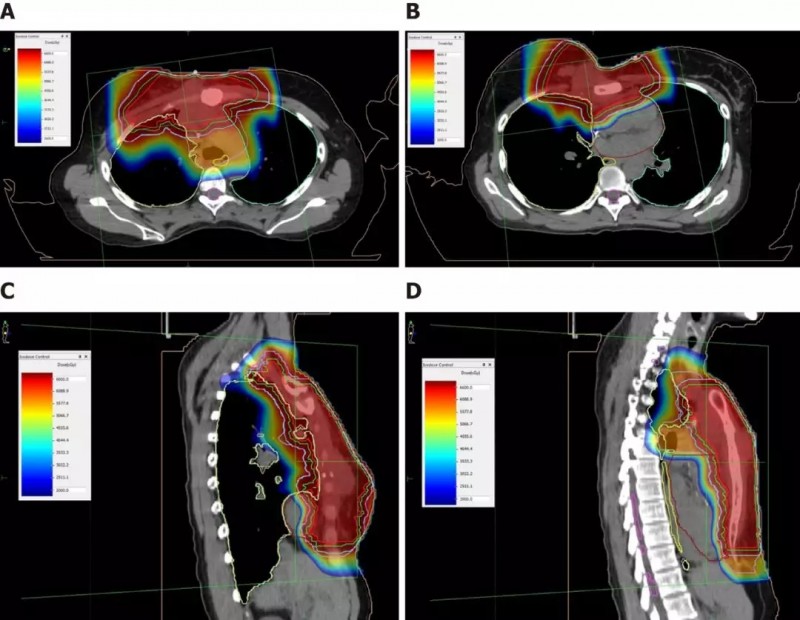

2016年11月至12月,Mary接受了右侧胸骨肿瘤以及邻近胸膜,右侧腋窝,胸骨旁和纵隔区域的淋巴结转移的质子放疗。

基于布拉格峰的物理学优势,质子束疗法(PBT)能够为局部复发的乳腺癌患者提供 的再放疗计划。不仅可以保护相邻的未受累的乳房组织和其他危险器官(OAR),如心脏,食道,肺,脊髓和神经,还可以使照射剂量增加到局部乳房和胸壁病灶 。